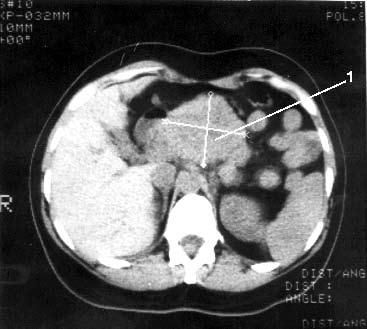

Рис. 99. Компьютерная томография. Рак головки ПЖ. На снимке видна гиподенсная бугристая опухоль головки ПЖ 4x5 см (1)

Дифференциальная диагностика рака, других опухолей ПЖ и псевдотуморозного хронического панкреатита (ХП) по данным КТ и УЗИ довольно сложна и часто невозможна. Наличие кист в области опухолевого образования, панкреатическая гипертензия встречаются в обоих случаях и не являются дифференциально-диагностическими признаками. Кальцинаты в проекции опухоли при РПЖ встречаются нечасто. В 95 % кальциноз свидетельствует о ХП. Для выявления опухолей ПЖ КТ предпочтительнее, чем УЗИ, так как дает больше информации о распространении опухоли на смежные анатомические структуры и его результаты не столь зависимы от опыта врача, выполняющего исследование. УЗИ и КТ – взаимодополняющие исследования и их следует применять вместе. В комбинации это позволяет повысить точность диагностики ракового поражения ПЖ до 90 %.